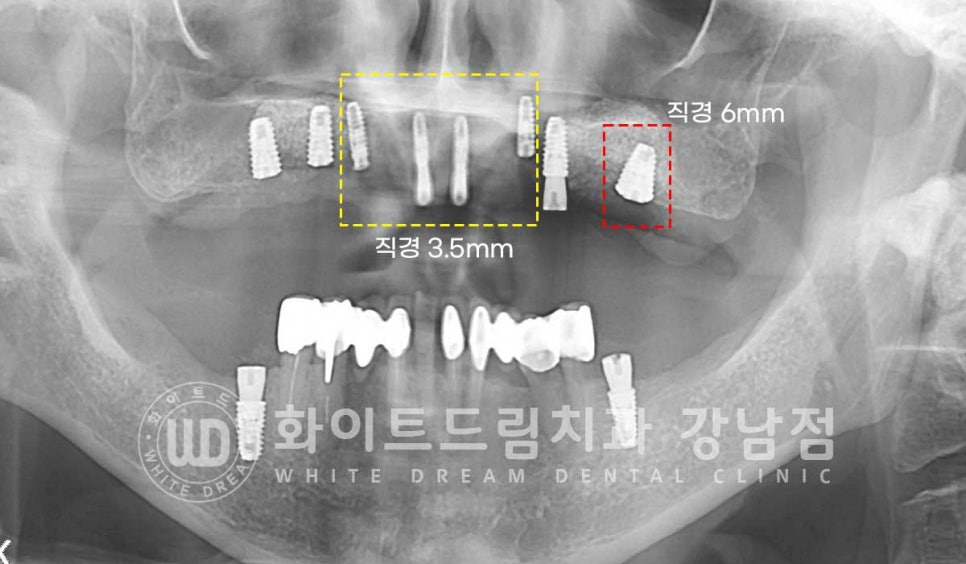

잇몸뼈의 골폭이 좁은 전치부는 직경 3.5mm의 미니 임플란트를 식립하고

어금니 부위는 직경 6mm의 와이드형 임플란트를 이용하여

고정력과 안정성을 높였습니다.

환자분처럼 6mm의 두꺼운 임플란트는 잘 사용하지는 않으나

초기 골 소실이 심해 고정력이 약한 경우는 직경이 넓은 임플란트를 선택하여

잇몸뼈와 접촉면적을 넓혀 고정력과 안정성을 높여주는 것도 하나의 좋은 선택이 될 수 있답니다.